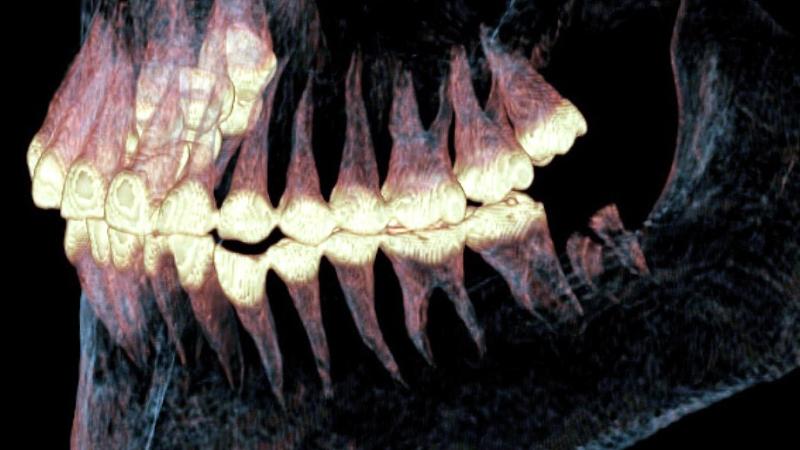

Сканирование на аппарате Philips MX 16 в Лаборатории ядерной и инновационной медицины Физического факультета НГУ выявило смещение и подвывих нижней челюсти, два просверлённых костных канала с уплотнением вокруг них и остатки эластичного материала, использованного для фиксации челюсти. Особенности зубного ряда и повышенная нагрузка на левую сторону подтверждают, что хирургическое вмешательство было успешным, и женщина прожила после него длительное время.

«Таким образом, компьютерный томограф выступил в роли «машины времени», обеспечив неразрушающий доступ к анатомическим структурам. Он позволил не только диагностировать травму, но и реконструировать результат сложного хирургического вмешательства, проведённого в глубокой древности, превратив единичную находку в детальное свидетельство высокого уровня медицинских знаний пазырыкской культуры», — рассказал заведующий Лабораторией ядерной и инновационной медицины ФФ НГУ Владимир Каныгин.